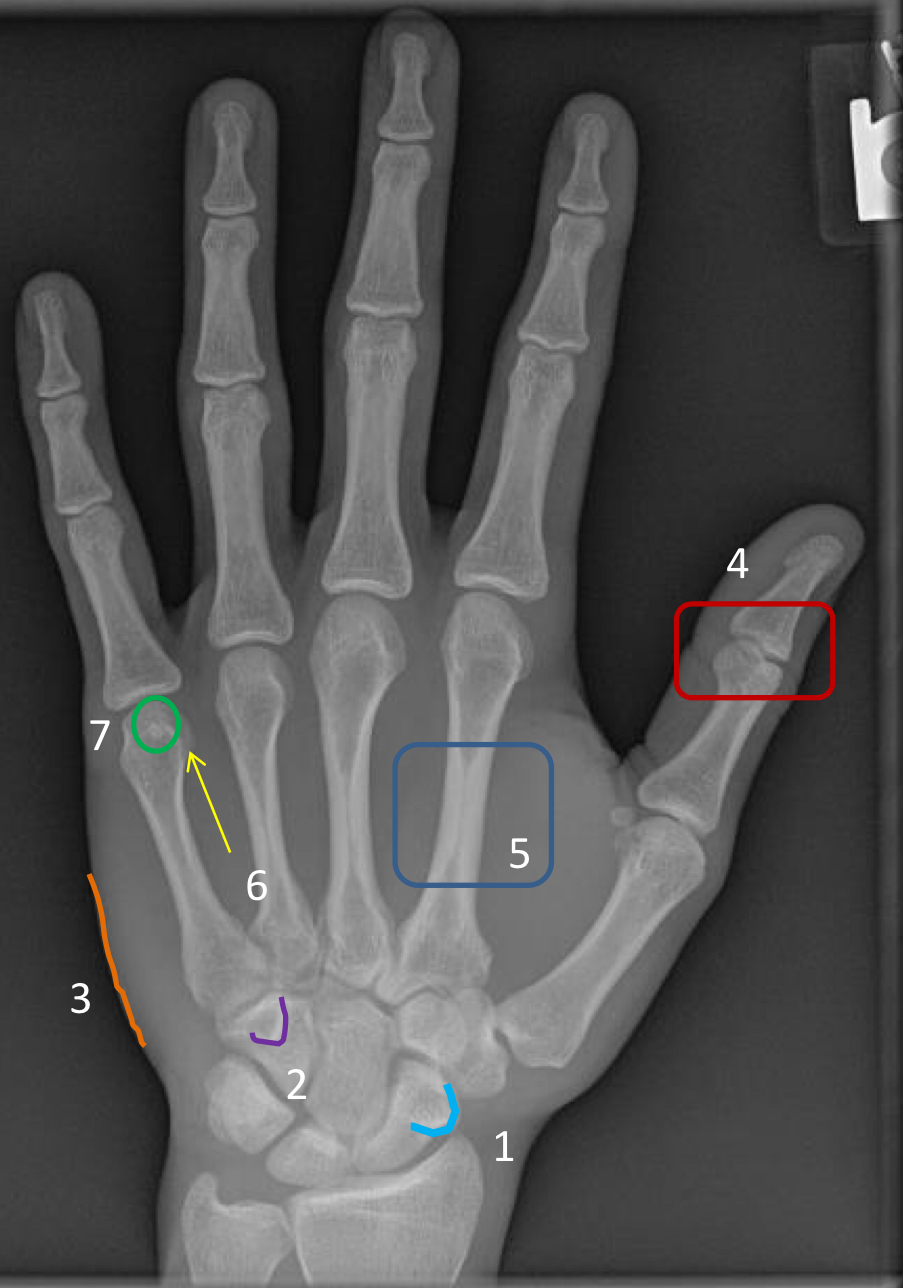

What view is this?

medial oblique

1?

ulnar styloid process

2?

proximal scaphoid

3?

scaphoid-trapezium joint space

4?

sesamoid at first metacarpal head

5?

1st ungual tuft

6?

sesamoid at 2nd metacarpal head

7?

3rd metacarpophalangeal joint space

8?

head of 4th metacarpal

9?

3rd proximal interphalangeal joint (not well visualized on oblique view)